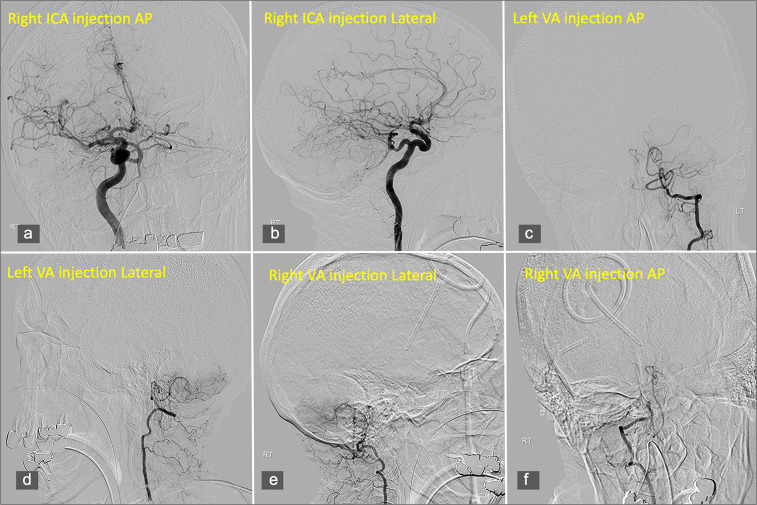

Case description: We present the case of a 77-year-old woman who experienced recurrent episodes of thunderclap headache, which eventually progressed to altered consciousness following admission. Neuroimaging revealed a SAH involving the fourth ventricle and basal cisterns, alongside cerebellar tonsillar herniation and obstructive hydrocephalus, with no arterial source identified on serial angiography. Magnetic resonance imaging confirmed CM1, with tonsillar descent to the C1 level. The patient underwent suboccipital decompression for refractory intracranial hypertension that prevented weaning from the external ventricular drain. Intraoperative exploration revealed an abnormal posterior spinal vein traversing the arachnoid membrane, which was suspected to be the source of the hemorrhage and was successfully coagulated.

Conclusion: To the best of our knowledge, this is the first documented case of CM1 presenting with recurrent SAH in the absence of aneurysmal or arteriovenous pathology. Our findings suggest a possible venous etiology related to anomalous posterior spinal venous drainage, which may have contributed to the hemorrhage and obstructive hydrocephalus. The patient's clinical improvement following Chiari decompression supports the role of surgical intervention in relieving cerebrospinal fluid outflow obstruction and elevated intracranial pressure in such cases. This case highlights the importance of considering venous anomalies in the differential diagnosis of non-aneurysmal SAH and underscores the need for heightened awareness of vascular variations in CM1 patients presenting with acute neurological symptoms.